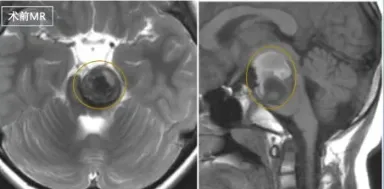

佩珊因左侧肢体无力就诊,确诊为脑干桥脑海绵状血管瘤出血。...